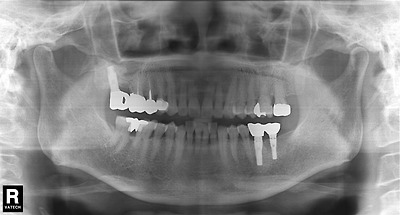

다음 두 사진에서 어떤 차이가 있는지 알아봅시다.

이미지를 클릭하면 원본을 보실 수 있습니다.

힌트; 36번 임플란트 보철물을 살펴보세요.

그래서 보철물을 재제작한 것이 아래의 사진입니다.

그렇다면 애초에 왜 이런 에러가 발생했을까요?

힌트; 이 임플란트는 '오스템 임플란트의 SS Type입니다.

SS 타입의 임플란트의 플랫폼은 직경이 4.8mm인 것과 직경이 6.0 인 것이 있습니다.

애초에 36번 임플란트는 4.8mm 직경의 플랫폼에 맞는 컴옥타 어벗먼트를 써야 했지만 6.0mm의 것을 선택했던 것이 원인입니다.

ss 타입에서 R과 W는 플랫폼이 4.8mm 직경이고

WP,WB는 6.0mm 플랫폼입니다.

W에서 6.0mm 플랫폼(와이드)의 임프레션 코핑이나 픽스쳐 아나로그를 쓰지 않고

레귤러 사이즈의 보철부속을 써야함을 명심해야 합니다.